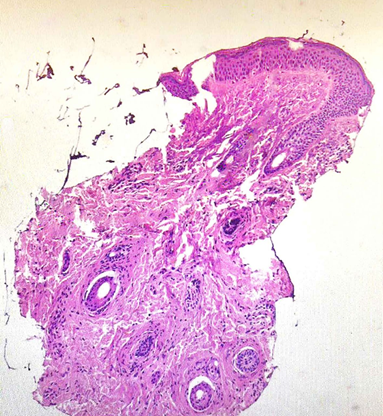

On days 5 and 7 following the procedure, the patients reported the persistence of micro papules in the periorbital areas. The papules were firm, non-painful, with minimal or no visible inflammatory reaction in the surrounding tissues. The patients A and B underwent follow-up consultations, massage and PRP (platelet-rich plasma) autologous injections were performed (Figure 1) (Figure 4). During consultation the status of the papules was evaluated using physical assessment with visual and palpatory control. The patients A and B underwent ultrasonographic examination on 13th day after collagen injection with a high-resolution 22 MHz Canon probe to determine the depth of the micro papules, which concluded the presence of the papules in subdermal layer. (Figure 2) (Figure 5A, B). The patient A underwent a tissue histology examination and 14th day after collagen injection to assess the nature of the papules, the reaction of the surrounding tissue, and the nature of the inflammation, which concluded that the papules are collagen collection without perifocal inflammation (Figure 3). Follow-up consultation was performed on day 28 after injection which concluded resolution of the symptoms, no visible or palpable papules were observed (Figure 5A & 5B).

Figure 3 The histopathological evaluation of Patient A skin biopsy specimen from right eyelid skin, stained with haematoxylin and eosin (H&E), demonstrates a cluster of collagen fibres localized within the dermis, extending into the hypodermis, with no evidence of perilesional inflammatory infiltrate.